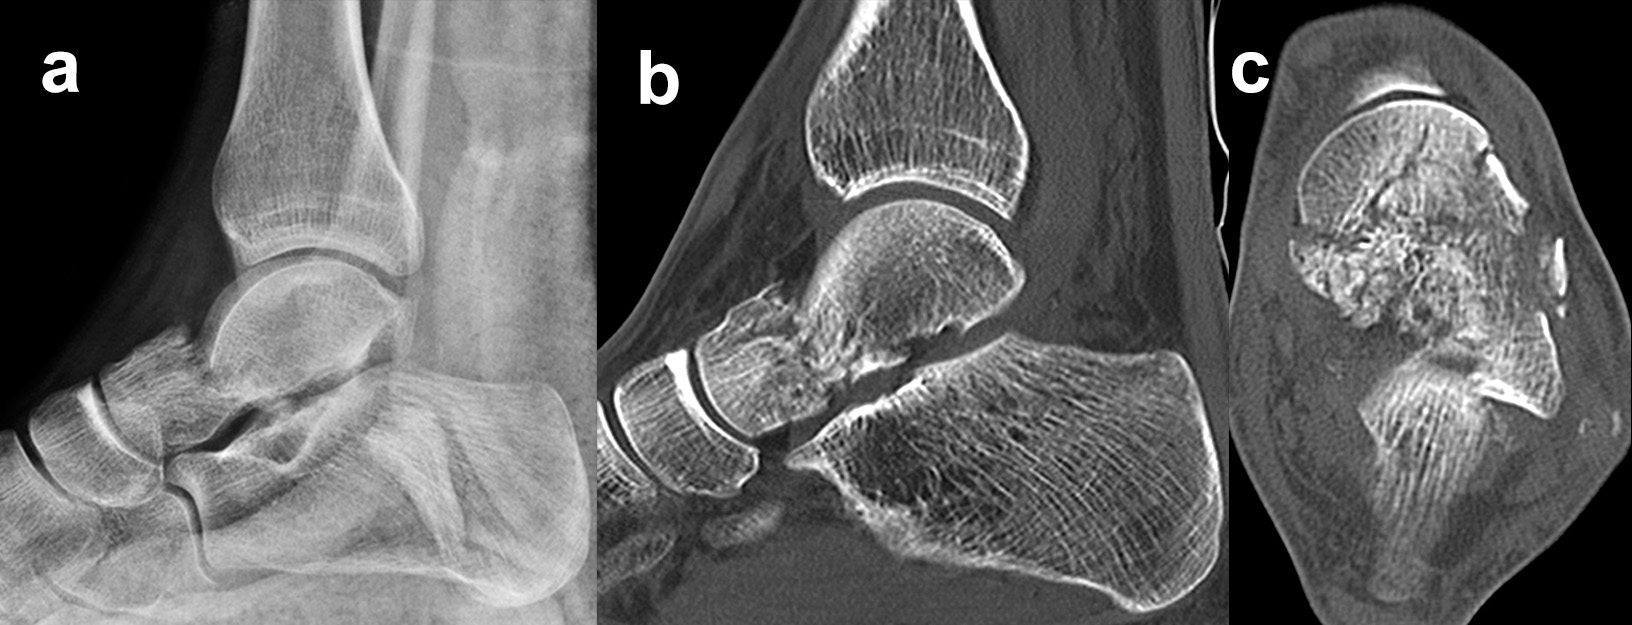

Die Zugänge zu dislozierten Taluskorpusfrakturen entsprechen im Wesentlichen denen bei Talushalsfraktur. Bei weit in den zentralen und hinteren Taluskorpus hineinreichenden Frakturen kann zur ausreichenden Übersicht und verbesserten Fragmentmanipulation eine Innenknöchelosteotomie erforderlich werden, sofern der Innenknöchel nicht ohnehin mit frakturiert ist 4. Hierzu wird der anteromediale Zugang nach proximal erweitert. Die Schraubenkanäle werden vorgeborht um eine exakte Refixierung des Innenknöchels nach der Talusosteosynthese zu gewährleisten. Die Osteotomie wird schräg auf den medialen Gelenkwinkel geführt, im eigenen Vorgehen zur besseren Stabilisierung vorzugsweise als Chevron-Osteotomie. Das Subtalargelenk ist bei Taluskorpusfrakturen regelhaft frakturiert und disloziert (Abb. 11). Zur Reposition und Überprüfung der Gelenkkongruenz im Subtalargelenk wird ein zusätzlicher anterolateraler Zugang benötigt.

Die anatomische Reposition erfolgt schrittweise unter direkter visueller Kontrolle von medial und lateral. Die temporäre Retention wird wiederum mit Kirschnerdrähten erzielt (Abb. 12). Die Hauptfragmente werden durch Schrauben, die unter Knorpelniveau versenkt werden, fixiert. Bei sagittalen Taluskorpusfrakturen werden daher vorzugsweise Doppelgewindeschrauben verwendet 34. Zur Fixierung kleinerer osteochondraler Fragmente werden vorzugsweise resorbierbare Stifte verwendet (Abb. 13). Zur Stabilisierung ausgedehnter medialer oder lateraler Trümmerzonen können anatomisch angepasste winkelstabile Platten verwendet werden. Bei diesen ist darauf zu achten, dass diese weder das Talonavicular-Gelenk noch den Innenknöchel irritieren. Gleiches gilt auch für Taluskopffrakturen, welche jedoch eher im Rahmen von Chopart-Luxationsfrakturen entstehen 12.

Zur Vollansicht und zum Lesen der Bildbeschreibung bitte die Bilder anklicken.